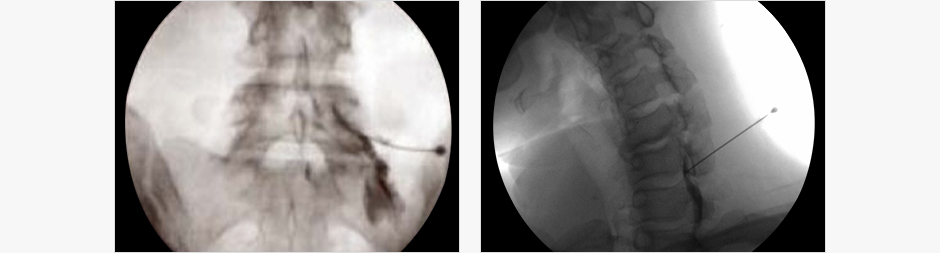

주사 방법

- 시술 시간은 10분 정도 걸립니다

- 투시경을 이용하여 화면으로 보며 신경주위까지 바늘을 넣어 주사합니다.

- 회복실에서 5~10분 정도의 안정을 취한 후에 퇴원합니다.

- 대개 주사는 환자의 증상에 따라 1~2주 간격으로 맞으며 3회 정도까지 시행합니다.

- 증상의 정도에 따라 추가적으로 시행할 수 있습니다